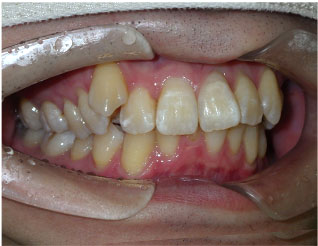

この方はクリアコレクトというマウスピース矯正で歯並び治療しました。 かなり外側に生えていた八重歯や引っ込んでいた下の前歯もきれいに整いました。 マウスピースは16枚、期間は8か月でした。